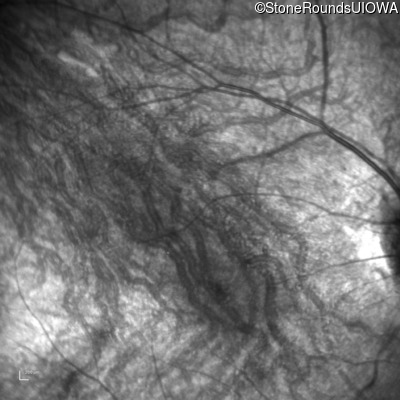

Infrared Fundus Photograph - Right - 10/300 sc

Exemplar